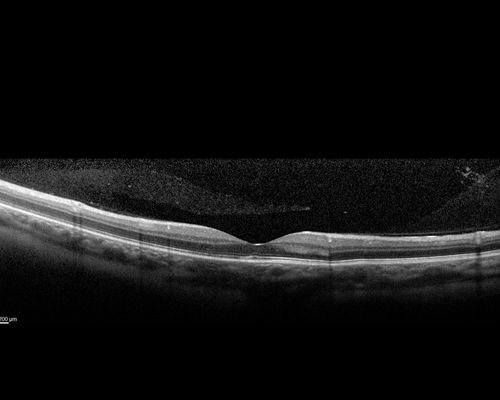

Multifocal Choroiditis - Pneumocystis - aspergillis - cryptococcus

31 year old male with anaplastic astrocytoma on chemotherapy with mild vision loss in the right eye.  LP did not reveal organism.  He was placed on a trial of anti-fungal medications and lost to follow-up